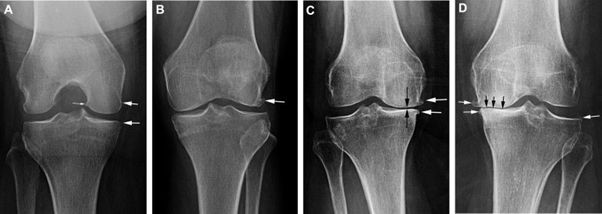

- Giai đoạn 1: người bệnh chưa thấy đau rõ ràng do sự mài mòn các thành phần chưa đáng kể, trên phim X-quang có thể thấy hình ảnh gai xương nhỏ.

- Giai đoạn 2: người bệnh có thể thấy đau gối sau khi đi bộ/chạy bộ quãng xa, đau khi quỳ gối, thấy hình ảnh gai xương rõ ràng trên phim X-quang.

- Giai đoạn 3: thoái hóa khớp gối mức độ trung bình. Người bệnh thấy đau gối thường xuyên khi đi bộ, chạy, gập gối, cứng khớp khi ngủ dậy, sưng khớp khi vận động liên tục, kéo dài. Trên phim X-quang thấy hẹp khe khớp rõ.

- Giai đoạn 4: thoái hóa khớp mức độ nặng, người bệnh cảm giác đau gối xuất hiện liên tục khi đi bộ hoặc cử động khớp, cứng khớp, sưng, nóng khớp gối theo đợt. Trên phim X-quang thấy hình ảnh hẹp khe khớp rõ kèm đặc xương dưới sụn.

A- Thoái hóa khớp gối độ 1: gai xương nhỏ.

B- Thoái hóa khớp gối độ 2: gai xương rõ ràng.

C- Thoái hóa khớp gối độ 3: Hẹp khe khớp.

D- Thoái hóa khớp gối độ 4: Hẹp khe khớp, đặc xương dưới sụn.